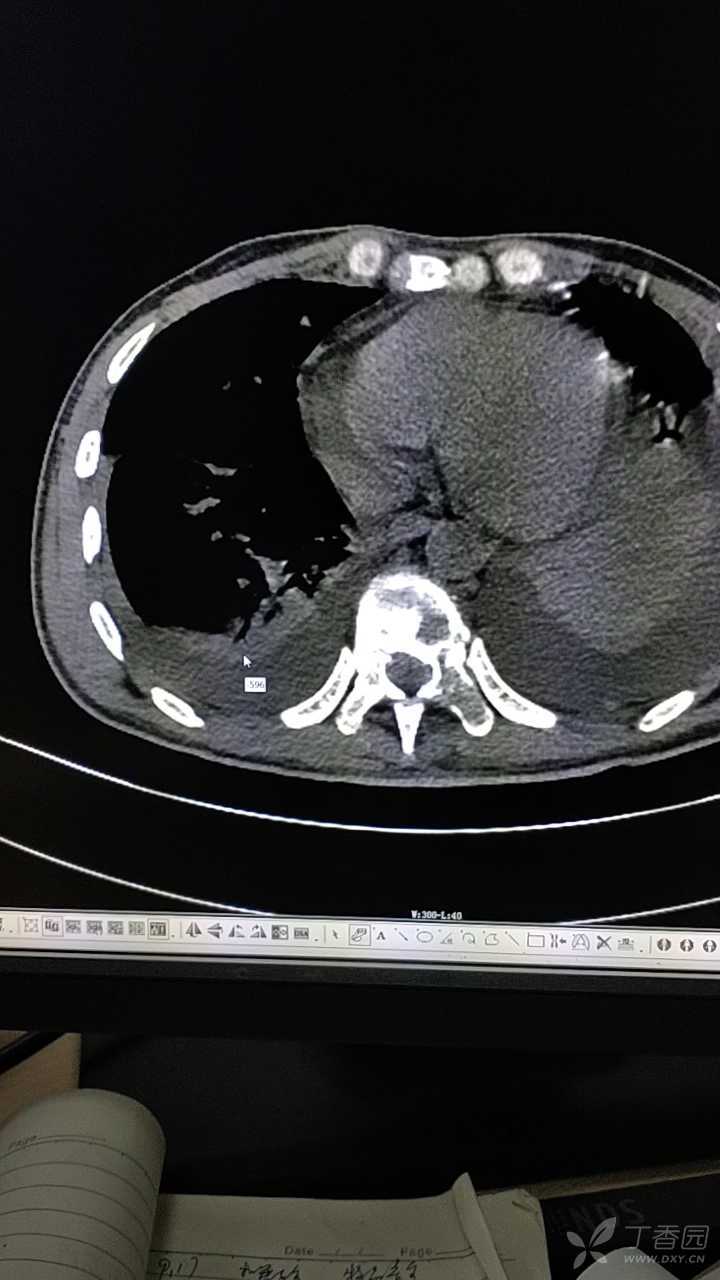

肺癌骨转移,疼痛vsa2分,双下肢麻木

图片尺寸3024x4032